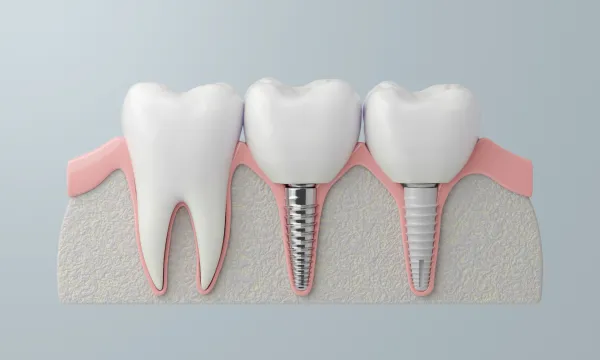

総入れ歯を使用されている方の中には、「しっかり噛めない」「外れるのが怖い」と不便を感じている方が多くいらっしゃいます。オールオンフォーは、片顎に4本前後のインプラントを埋め込み、その上に取り外し不要の固定式の人工歯を装着する治療法です。違和感を抑えつつ安定感のある噛み心地を得やすいのが特徴です。

さらに、従来はインプラント治療が難しいとされてきた骨量の少ないケースでも、サイナスリフトやソケットリフトといった骨造成を組み合わせることで、治療の可能性を広げられる場合があります。「もう入れ歯しかない」と言われた方でも、固定式の歯で新しい日常を取り戻せるチャンスがあります。

オールオンフォー/シックスでは、奥歯のインプラントを斜めに埋入する独自の方法を採用します。これにより骨のある部分を有効に使い、片顎4~6本という少ない本数で全体を支えることが可能になります。

従来の治療では歯を失った本数に近い数のインプラントを必要とすることが多く、骨移植や大がかりな骨造成を伴うケースも少なくありませんでした。これに対しオールオンフォー/シックスは、骨の状態を最大限活かしながら安定した支持を得られるのが大きな特徴です。

さらに、インプラントは骨と結合する性質があるため、強固な土台として機能します。その上に装着する人工歯は色や形を調整でき、自然で快適な仕上がりを目指せます。